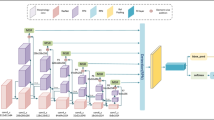

In modern medical applications, computed tomography image is used as one of the most useful tools for diagnosis and localization of lesions. It can provide patients with precise information about the location and size of their tumor lesions. Traditional medical diagnosis is not only very time consuming but also not very accurate. Nowadays, the automatic detection of lesions on computed tomography has become a research area of great interest, and researchers aim to use computer-aided diagnosis to assist in clinical medical diagnosis. However, for current detection algorithms, the accuracy of automatic lesion detection is still low, especially for small lesions. In this paper, to improve the accuracy of detection of small lesions, we propose a Multi-Scale Response Module (MSR) that incorporates global attention into Feature Pyramid Network (FPN) build on backbone. At each pyramid level, the proposed Aggregated Dilation Block (ADB) is used to capture the variations in the fine-grained scales. The response of the network to small lesion features is then reinforced by the Global Attention Block (GAB). We build a Feature Pyramid Network (FPN) based on the highly responsive output of the MSR module, with each layer of the FPN fusing high semantic information from low resolution layers. The experimental results show that our method has a higher detection accuracy with mAP value of 58.4 and a high sensitivity compared to the state-of-the-art methods.